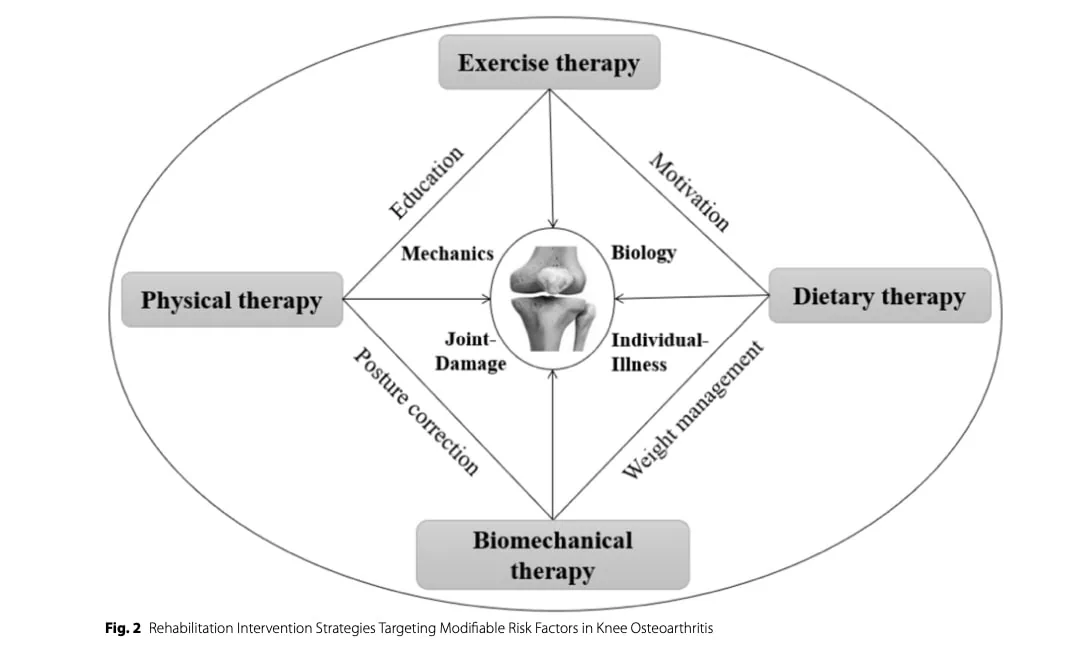

风险因素和保守治疗

膝关节骨关节炎的风险因素众多,包括生物力学因素、缺乏运动、肥胖、肢体排列异常以及先前的关节损伤或创伤。 保守治疗 膝关节骨关节炎康复的保守疗法 应旨在减轻这些可改变的风险因素。 除治疗性运动外,一些学者还提出了支具、矫形鞋垫、活动度辅助工具和特定物理治疗方法(如超声波、体外冲击波疗法、脉冲电磁场和低强度激光疗法)等干预措施,作为潜在的相关辅助手段,但其效果参差不齐,应被视为运动康复的辅助手段。

饮食干预

体重管理在 膝关节骨关节炎康复中发挥着核心作用。. 研究表明,减轻 5-10% 的体重可明显减轻疼痛并改善功能。 减肥还与全身炎症标志物的减少有关,包括肿瘤坏死因子-α(TNF-α)、白细胞介素-6(IL-6)和C反应蛋白(CRP),这些标志物与软骨降解有关。

除了限制热量外,还应考虑营养质量。 富含欧米伽-3 脂肪酸的膳食通过调节炎症通路表现出消炎特性,有助于减轻疼痛和改善功能。 富含纤维的膳食通常来自水果和蔬菜,与降低全身炎症有关,还能提供维他命 C 和 E 等抗氧化剂,从而降低氧化压力和炎症活性。

生物力学方法

膝关节负荷分布的改变会增加关节软骨的机制压力,导致症状进展。 因此,旨在优化下肢对齐和减少关节过度负荷的干预措施可改善疼痛和功能。 值得注意的是,已发现步态期间膝关节内收力矩增加与疼痛严重程度、疾病进展和内侧间室退化之间存在关联。

矫形器,包括鞋垫、膝关节支具和行走辅助器,可减少膝关节受到的机制约束。 侧面楔形鞋垫可通过侧面转移地面反作用力来减少膝关节内收力矩,可能特别适用于膝关节屈曲和内侧骨关节炎患者。 然而,目前支持将鞋垫用于 膝关节骨关节炎康复的证据仍然无力且不一致,这可能是由于患者表现和生物力学反应的异质性。

物理治疗师干预

物理治疗师在采用生物心理社会方法治疗膝关节骨关节炎方面发挥着核心作用。 全面的评估应包括对关节力学、运动范围、肌肉力量、本体感觉和步态的评估,并辅以临床病史和经过验证的结果测量,如 WOMAC 和 SF-36。